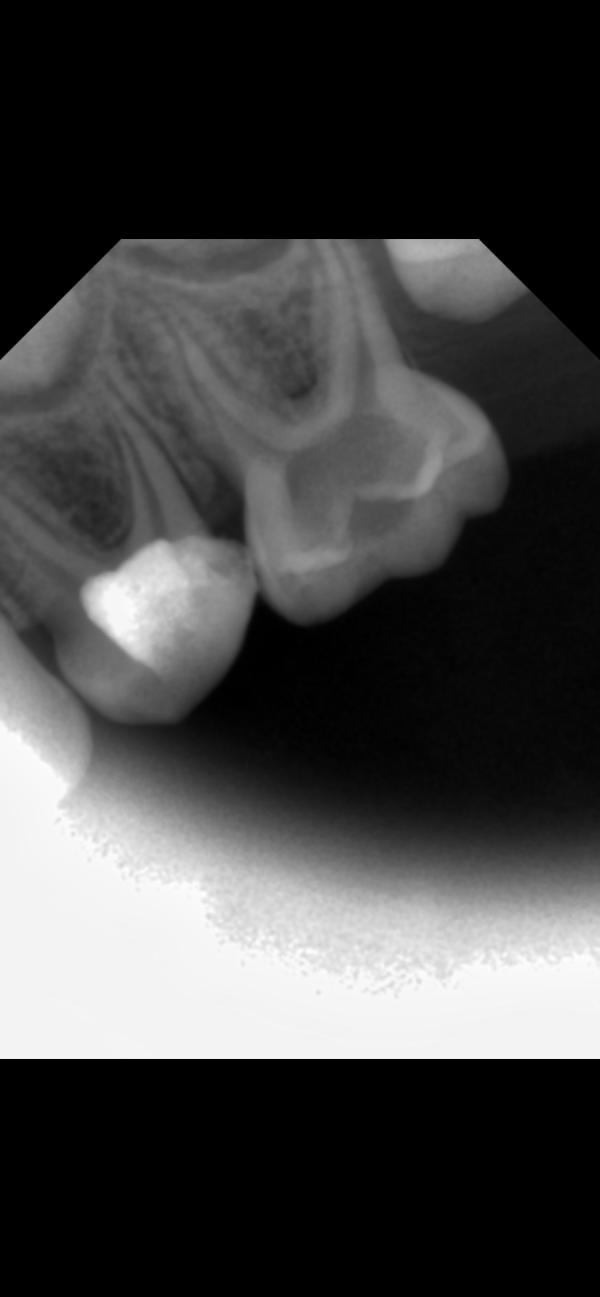

@isdarja, да, где затемнение на корне. У обоих единичек корни рассасываются уже, смысла их лечить никакого по сути нет. Но тот, что с воспалением, может повредить зачаток постоянного

Левую единицу удалять 100%. Остальные хорошо бы переделать снимки в другой проекции, не совсем понятно